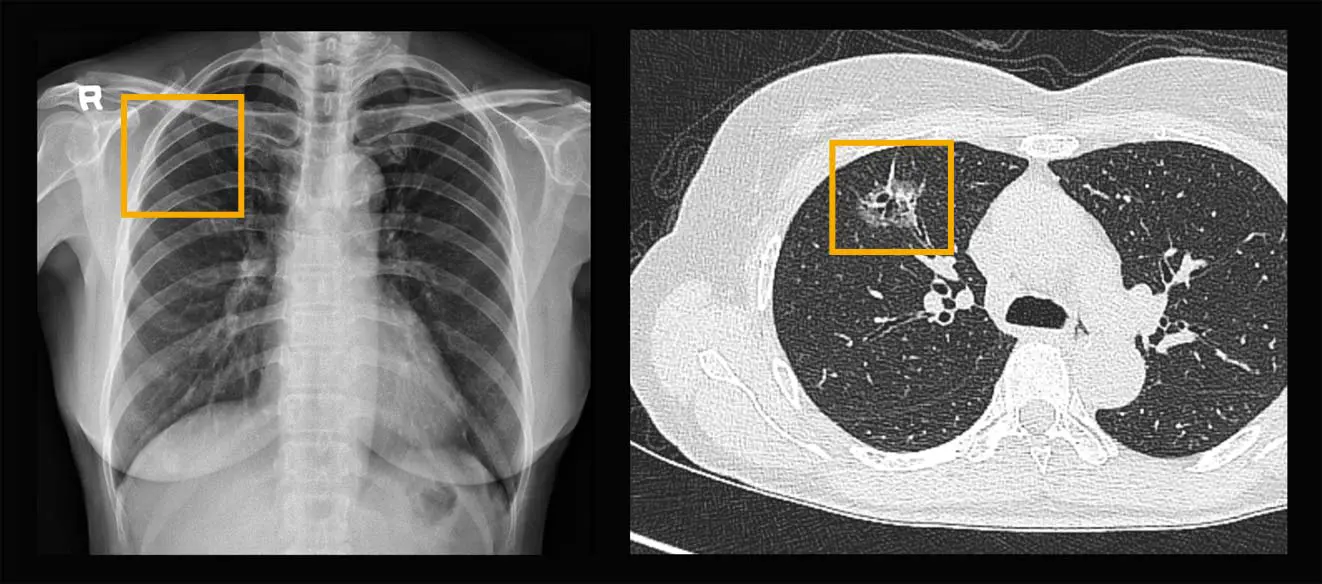

일반 X-레이 촬영과 저선량 폐CT 사진 비교

본원에 내원하신 무증상의 60대 여성(과거 흡연 후 금연 10년차)의 경우, 좌측 흉부X-레이 촬영에서는 특이 소견이 발견되지 않았으나, 문진 후 저선량 폐CT 촬영을 통해 폐 선암을 확인할 수 있었습니다.